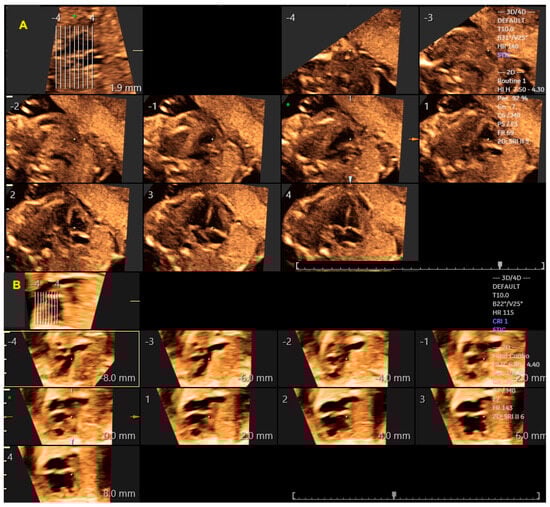

The advent of advanced imaging technologies, such as three-dimensional (3D) ultrasound in the early 1990s and, in particular, Spatiotemporal Image Correlation (STIC) software in the early 2000s, enabled major technological advances in the 3D assessment of the fetal heart. STIC technology, as first described by De Vore et al. [3], involves the acquisition of approximately 150 two-dimensional images per second using a volumetric transducer during a single 7.5 to 15 s scan. The acquired 3D volumes contain a “block” of cardiac ultrasound images that allow the detailed analysis of cardiac anatomy (Figure 1A) [4]. This technology also provides measurements of the areas of the fetal heart valves and the volumes of the chambers and myocardial walls (Figure 1B). Some of the advantages of STIC in the assessment of the fetal heart include less operator dependence in obtaining ultrasound views of the heart, a shorter scan examination time, as the volume analysis can be performed in the absence of the pregnant woman (offline), and the ability to send the heart volumes via an Internet link for review by experts in tertiary centers (tele-STIC) [5,6].

To obtain a cardiac volume using the STIC method, the examiner must obtain a 4C view of the fetal heart, whenever possible, with the fetal spine positioned as close to 6 o’clock as possible. Ideally, this image acquisition should be performed with the pregnant woman in apnea for a few seconds and the fetus at rest. The settings for this acquisition are: an opening angle between 20° and 40° and an acquisition time between 7.5 and 15 s according the gestational age [17]. By adjusting the brightness and color, STIC in the rendering mode allows the detailed evaluation of cardiac anatomy and measurement (area and volume) of a variety of structures of the fetal heart, such as the interventricular septum, valves, and papillary muscles [18,19,20,21,22]. STIC technology can reconstruct moving images and display them in grayscale, Doppler mode (inversion mode/color Doppler), B-flow imaging, and Tomographic Ultrasound Imaging (TUI) [23,24,25,26] (Figure 4, Figure 5 and Figure 6).

Figure 4.

Spatiotemporal Image Correlation with Tomographic Ultrasound Imaging (TUI) technique, providing automatic slices with visualization of the sequential axial views of a normal heart (A) and in the case of atrioventricular septal defect with double right ventricle outflow tract (B). Interslice distance 4 mm; * 0 mm. Asterisk and arrows: Automatic slices 4 mm * point 0.